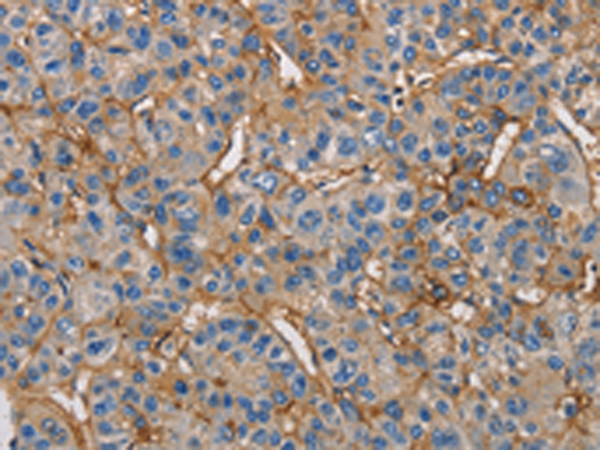

分类: 科研抗体货号: P08010别名: ZFYVE11; FYVE-DSP2应用: IHC反应种属: Human, Mouse